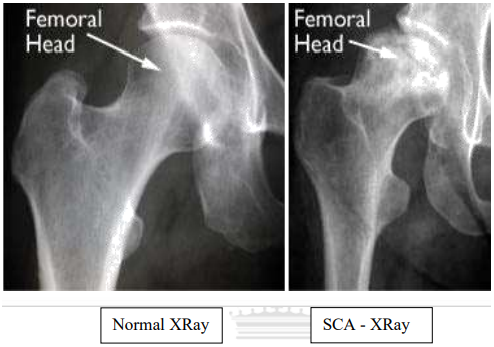

Диагностика ТБС рентгеном и асептический некроз: особенности лечения

Раздел: Снимки-откровения